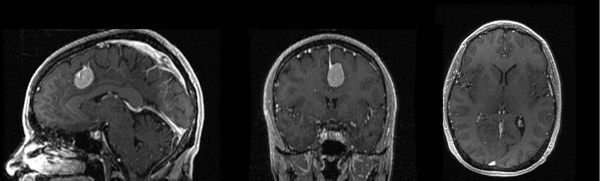

Slicer Registration Use Case Exampe #2: Inter-subject Brain MRI: axial T1 Tumor Growth Assessment

This is a classic case of change assessment. We want to know if the tumor changed since last exam.

MRI, brain, head, intra-subject, T1, tumor growth, meningioma, change assessment

• Button red fixed white.jpgreference/fixed : T1 SPGR , 0.9375 x 0.9375 x 1.4 mm voxel size, axial, RAS orientation.

• Button green moving white.jpg moving: T1 SPGR , 0.9375 x 0.9375 x 1.2 mm voxel size, sagittal, RAS orientation.